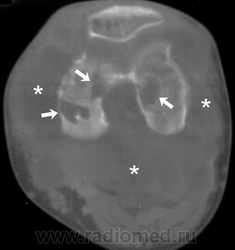

Хондросаркома синовиальная Пт, 21/09/2012 - 04:01 #1 Дмитрий86 Не на сайте Был на сайте: 11 месяцев 3 недели назад Зарегистрирован: 17.01.2012 - 08:49 Публикации: 285 пффф, на 1 снимке что стрелками указано можно принять за простые кальцинаты, а то что позади бедренной за сесамовидку.